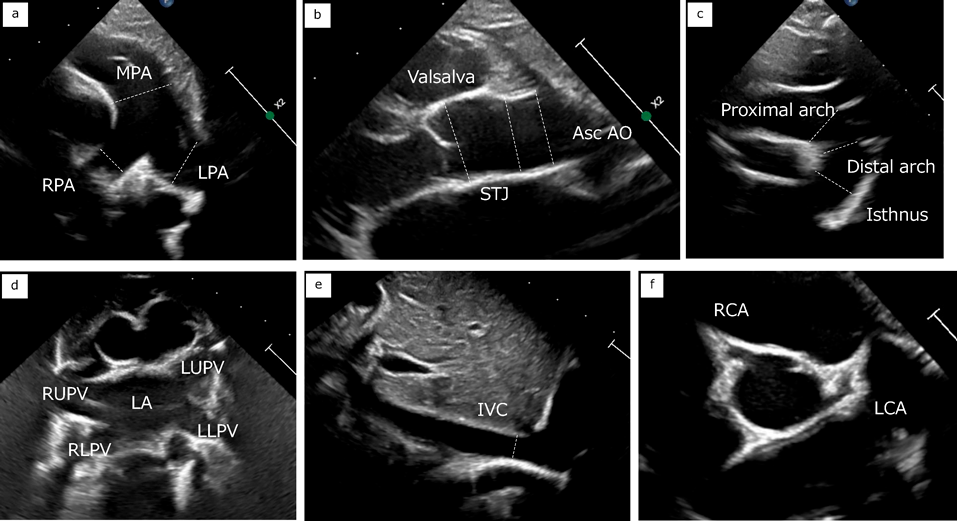

それぞれの弁輪と血管の計測を示す(Figs. 5, 6).いずれも最大となる時相で内膜面間の距離(trailing edge to leading edge)を計測する.僧帽弁輪径,三尖弁輪径は心尖部四腔断面と傍胸骨長軸断面でそれぞれ計測する.最大径となる拡張期で弁付着部を計測することが一般的であり,楕円形の房室弁輪形態を反映してそれぞれの計測部位で正常値が異なる.大動脈弁輪径は傍胸骨長軸断面で計測し,最大径となる収縮期で計測する.同様にバルサルバ洞径,接合部径,上行大動脈径も計測するが,これらの部位は成人ガイドラインにおいて拡張末期にleading edge to leading edgeでの計測が推奨されており,施設内での統一が望ましい.肺動脈弁輪径は収縮期の傍胸骨短軸断面で計測し,主肺動脈径,左右肺動脈径の計測も行う.症例によっては傍胸骨長軸断面のほうが描出しやすいことがある.大動脈弓は胸骨上窩断面から体位の工夫を併用して描出し,近位(無名動脈–左総頚動脈間),遠位(左総頚動脈–左鎖骨下動脈間),峡部(左鎖骨下動脈以遠の最狭部)を計測する.下大静脈は心窩部断面で下行大動脈との位置関係と流入する心房を確認し,右房に連続する断面で計測するとともに呼吸による変動を観察する.肺静脈は心尖部断面と胸骨上窩断面で左房への流入を確認する.冠動脈は傍胸骨短軸断面の大動脈弁レベルから左右冠動脈起始部を描出し,流速を下げたカラードプラを併用する.

Pediatric Cardiology and Cardiac Surgery 41(1): 20-27 (2025)

Fig. 6 Measurements of vessels

a. Mein, right and left pulmonary artery. b. Valsalva, ST junction, ascending aorta. c. Arch. d. Pulmonary veins. e. Inferior vena cava. f. Coronary artery. Asc Ao, ascending aorta; IVC, inferior vena cava; LA, left atrium; LCA, left coronary artery; LLPV, left lower pulmonary vein; LPA, left pulmonary artery; LUPV, left upper pulmonary vein; MPA, main pulmonary artery; RCA, right coronary artery; RLPV, right lower pulmonary vein; RPA, right pulmonary artery; RUPV, right upper pulmonary vein; STJ, sinotublar junction.